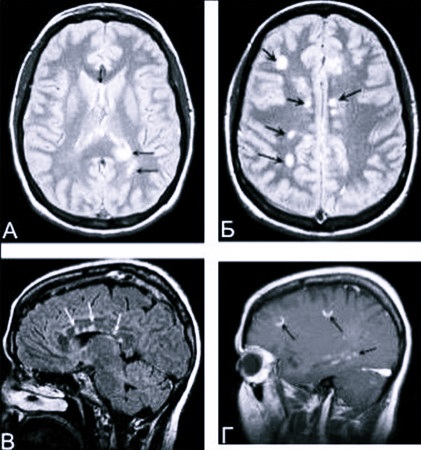

Чтобы обеспечить качественное лечение, важно установить точный диагноз. Он должен отражать вид заболевания, его причину. При диагностике могут применять такие методы:

- МРТ;

Нужно постоянно контролировать, как организм отвечает на лечение, как развивается заболевание. Чтобы выявить очаги демиелинизации, регулярно используют МРТ. Также исследуют кровь, определяя состояние иммунной системы.